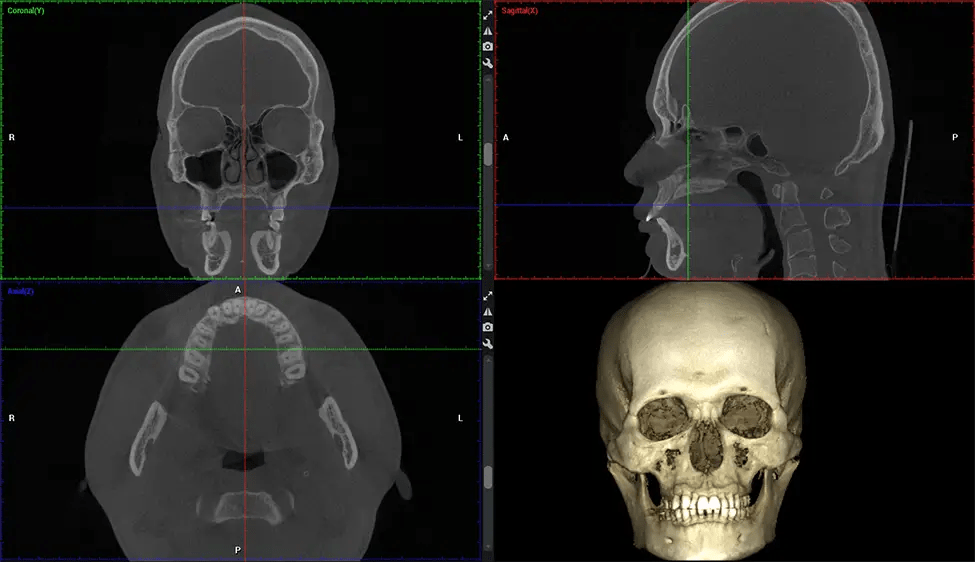

La tomografía computarizada de haz cónico (CBCT) es una técnica de imagen avanzada utilizada en odontología y cirugía maxilofacial para obtener imágenes detalladas en 3D de las estructuras orales y maxilofaciales. En Dr G Dental Studio, nuestros escáneres CBCT utilizan un haz de rayos X en forma de cono y un detector especializado para capturar imágenes desde diferentes ángulos. Luego, una computadora combina estas imágenes para crear una representación 3D de la anatomía oral del paciente.

Esta exploración 3D, llamada tomografía computarizada de haz cónico, le brinda a su dentista una imagen más completa de su anatomía bucal y sus procesos patológicos que una radiografía tradicional. A diferencia de las radiografías convencionales, que capturan una imagen 2D de la boca desde varios ángulos, una exploración 3D toma varias radiografías digitales para una imagen. Proporciona una vista completa de la mandíbula, los dientes, los nervios y los tejidos blandos. Esta vista mejorada permite a los dentistas detectar problemas menores que no son visibles en las exploraciones 2D tradicionales, como muelas del juicio impactadas o fracturas óseas en la cavidad sinusal.

Después del proceso de escaneo, las imágenes de rayos X capturadas son procesadas por el software CBCT, que aplica algoritmos para reconstruir una imagen 3D detallada del área escaneada. El software recopila estas imágenes de rayos X individuales y crea una representación digital en 3D de la anatomía del paciente. El dentista o el radiólogo pueden ver y analizar la imagen CBCT 3D reconstruida. Esta imagen se puede manipular, rotar y acercar o alejar para examinar estructuras específicas y evaluar la condición del paciente.